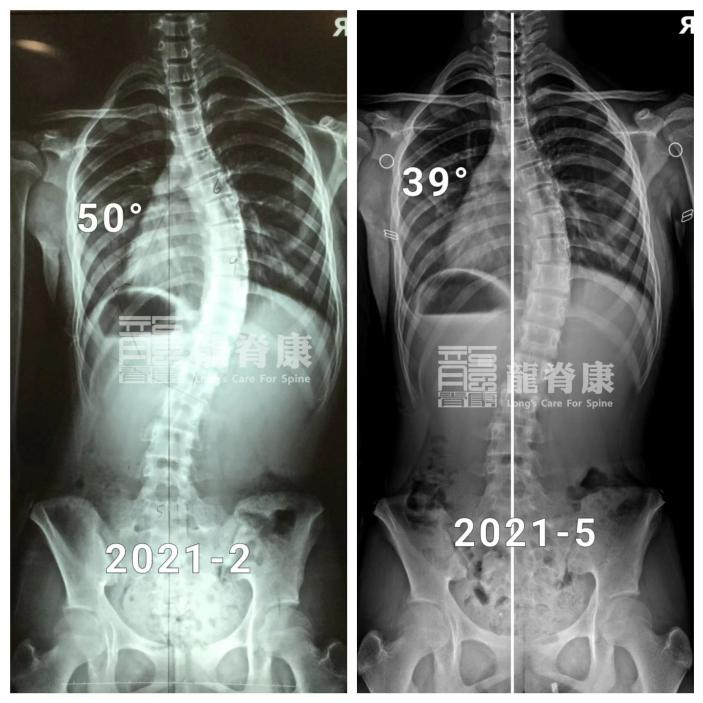

在最初的一年里,小墨坚持每3个月回来复查体态以及调整支具。3个月复查时,脱支具4小时后的X光片显示,她的胸弯度数已经从50°减至39°,且剃刀背都有明显改善,右背部剃刀背由14°减至7°,左腰部剃刀背由12°减至8°。

矫正的第二年,无论是她的侧弯度数还是体态,还是有在慢慢好转,只是改善速度明显不及第一年了。

尽管如此,胸弯角度由50°减少至31°的小墨已经能避免了手术治疗;接下来的时间里,在她骨骼发育基本成熟稳定前,小墨还是需要继续配合治疗以及及时复查,除稳定侧弯减少进展的风险外,她还能为进一步改善体表再努力一把。